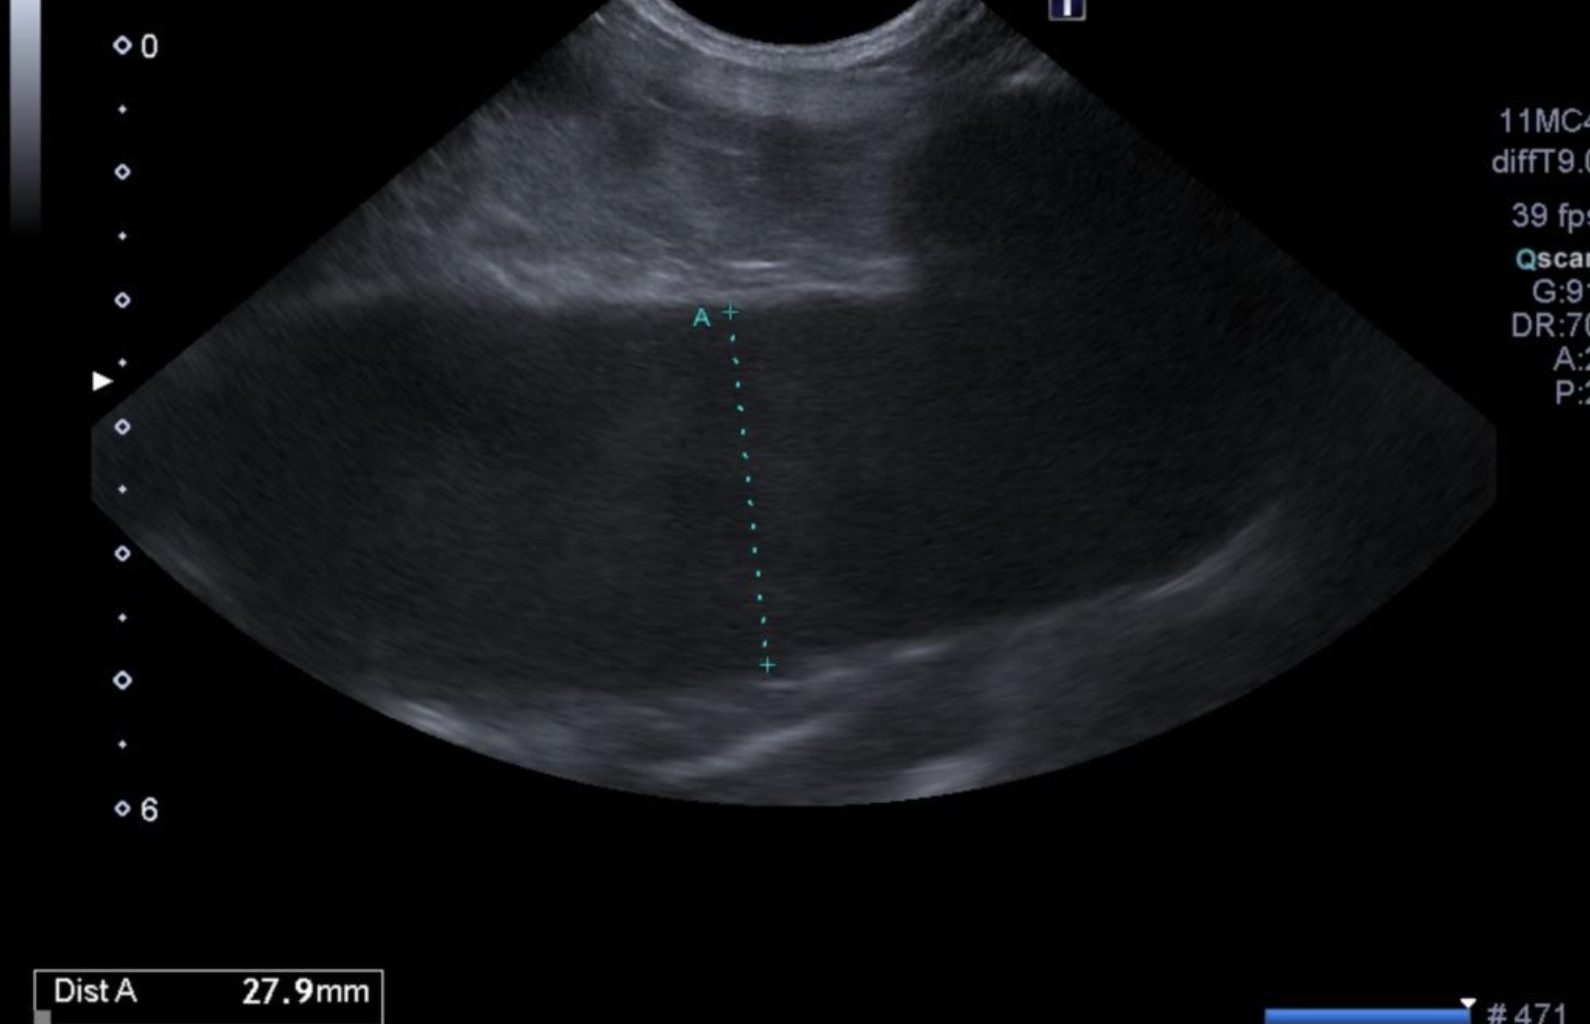

↑子宮内に膿が溜まって拡張している様子

レントゲン検査、超音波検査(子宮の腫大や膿の貯留確認)